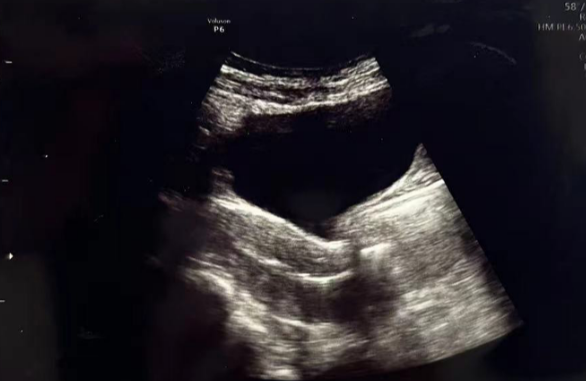

在进行3毫升的子宫峡部切口冲洗后,经过经腹超声检查显示子宫内膜呈三线状,且子宫腔内未见液体。

术后给予抗生素预防感染,为后续胚胎移植扫清子宫环境障碍。

• Pre-Irrigation灌洗后: